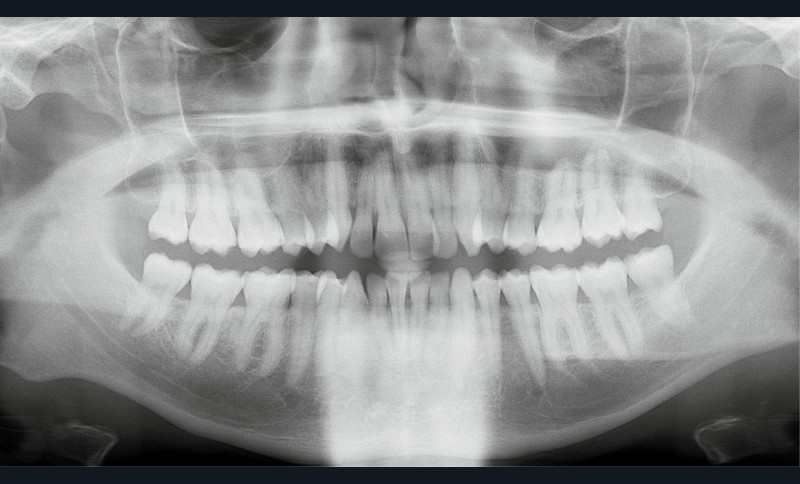

Diagnostic (fig. 1a-i)

Le patient consulte initialement pour des défauts d’alignement. L’examen clinique confirme l’existence d’un encombrement antérieur bimaxillaire, mais révèle aussi la présence d’une Classe II dentaire sévère, d’une exoclusion de la 27 et de troubles parodontaux (peu ou absence de papilles inter-dentaires). Sur le plan squelettique, le patient est relativement équilibré avec un profil harmonieux.